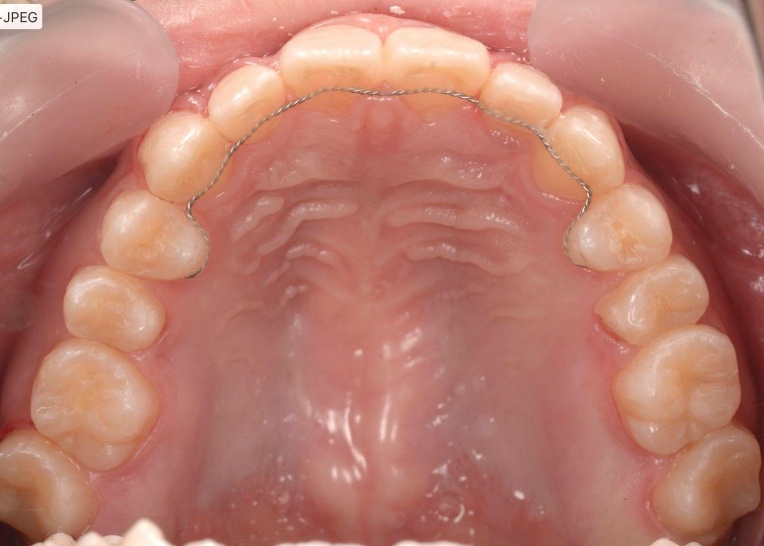

「前歯が噛み合わないので治したい」とご相談いただきました。 |

拝見したところ、重度の開咬(かいこう)が認められました。 |

見た目と噛む機能の両方を改善するため、矯正治療を提案し、同意いただきました。 |